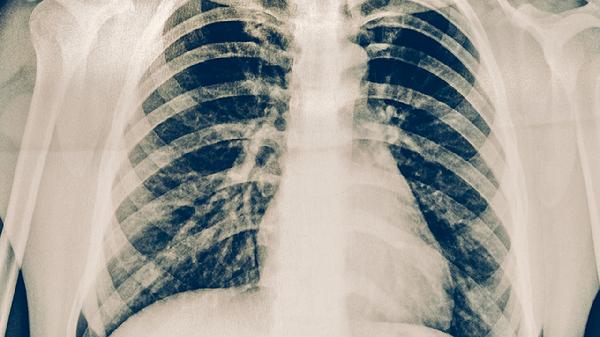

支气管癌是起源于支气管黏膜的恶性肿瘤,主要与长期吸烟、空气污染、职业暴露、遗传易感性及慢性肺部疾病等因素相关。

石棉、砷等职业接触或PM2.5污染导致支气管黏膜DNA损伤。治疗采用多学科综合疗法,免疫检查点抑制剂帕博利珠单抗对PD-L1高表达患者效果显著,放射性粒子植入可局部控制肿瘤进展。高危职业者需定期低剂量CT筛查。